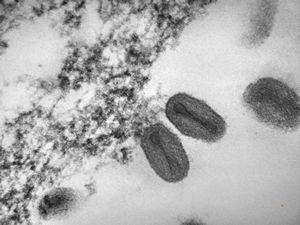

F, 24y. | molluscum contagiosum … virions